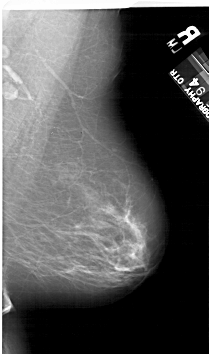

A_1124_1.LEFT_MLO

LEFT_MLO LINES 6196 PIXELS_PER_LINE 3616 BITS_PER_PIXEL 12 RESOLUTION 43.5 OVERLAY

FILE: A_1124_1.LEFT_MLO.OVERLAY

TOTAL_ABNORMALITIES 1

ABNORMALITY 1

LESION_TYPE CALCIFICATION TYPE PLEOMORPHIC DISTRIBUTION LINEAR

ASSESSMENT 4

SUBTLETY 1

PATHOLOGY MALIGNANT

TOTAL_OUTLINES 1

BOUNDARY